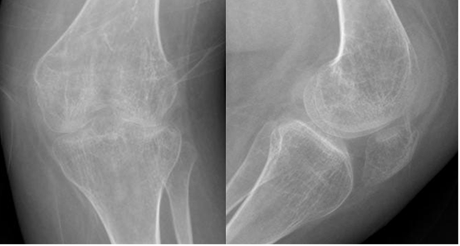

Fig 192. Artritis reumatoidea.

A: Rx AP y B: Rx lateral de rodilla. Osteopenia generalizada, con pérdida de los espacios femorotibiales y ausencia de osteofitos. Deformidad en valgo asociada.